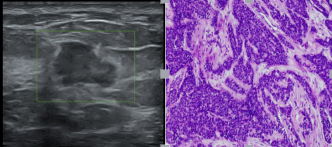

▲超声提示:右侧乳腺结节(BI-RADS 4级)

术后病理提示浸润性乳腺癌